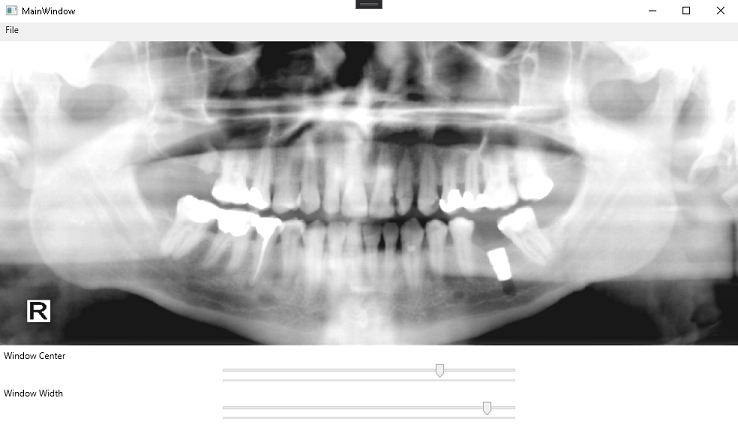

Run the project by pressing F5 or by selecting Debug -> Start Debugging.

If the steps were followed correctly, the application should run and display an empty ImageViewer. To test, follow the steps below:

-

Click on File -> Open to bring up the OpenFileDialog.

-

Select a

.dcmimage to be loaded into the ImageViewer. This tutorial uses the DCM file in the following file path:C:\LEADTOOLS23\Resources\Images\DICOM\image2.dcm -

Use the sliders at the bottom of the window to change the window level and center.